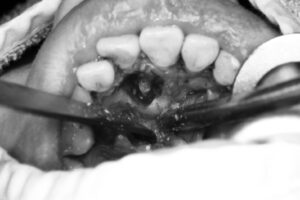

1. 口腔外科で過剰歯の抜歯手術

😄無事に治療を終え、矯正治療スタート!

抜歯手術も無事に終わり、経過良好✨

現在は矯正装置を装着し、治療を順調に進めている段階です!